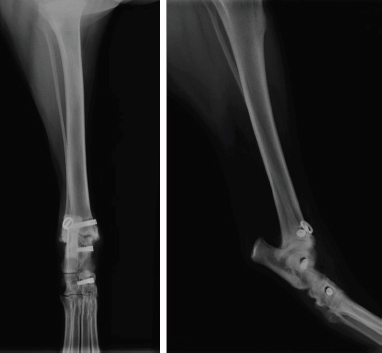

The surgical site was then closed plane by plane. Immediate postoperative radiographs showed a good implantation of the interference screws in the bone drillings through the distal tibia and the talus. However, the bone drilling corresponding to the distal insertion of the long head of the MCTL was not satisfactory: it was drilled between the tarsal midbone and tarsal bones II and III, while it should have been drilled through the tarsal midbone (Fig. 6).

An approximation in the third drilling (distal reconstruction of the long head of the MCTL) was observed during the immediate postoperative radiographic control (Fig. 6). No other intraoperative complications occurred. Unfortunately, postoperative advice was not followed properly. The bivalve resin boot was completely removed at only 2 weeks postoperatively. However, a first radiographic check at 11 weeks showed good valgus stability of the tibiotarsal joint and the orthopedic examination showed a return to subnormal function of the pelvic limb during locomotion. At 12 months postoperatively, valgus stability of the tibiotarsal joint was maintained and the pelvic limb returned to normal function during locomotion. At 16 months post-op, radiographic control showed ovalization of the bone tunnels with no clinical impact on the stability of the tibiotarsal joint (Fig. 7).

Avulsion of the long head of the left MCTL was diagnosed in a five-year-old overweight castrated male Australian Shepherd. The context was favorable to the implementation of the surgical ligament reconstruction technique previously described. Although the immediate postoperative radiographic control showed an approximation of the third drilling (distal reconstruction of the long head of the MCTL), the surgeon chose not to reopen the surgical site (Fig. 6). The reason for this choice was that sufficient tightening torque was perceived by the veterinary surgeon during the implantation of the 4x13-mm interference screw, which was compatible with satisfactory primary fixation of the UHMWPE implant according to his empirical experience. Although external restraint was maintained for only 2 weeks and the animal did not lose weight as advised, no postoperative complications were identified and one year after surgery, the animal regained normal locomotion. This synthetic MCTL reconstruction technique thus allowed a complete and durable functional and clinical recovery without the need for invasive transarticular immobilization, such as the placement of a transarticular external fixator (TEF). However, the use of a bivalve resin boot was recommended for a minimum of 6 weeks, which was not respected. In addition, the animal did not lose weight as advised. Early weight-bearing on the limb without any other form of restraint and the excess weight were potentially the cause of the progressive ovalization of the tunnels observed on the radiographic images taken 16 months postoperatively. In humans, obesity has been shown to be a leading risk factor for intraoperative complications in total hip arthroplasty (Haynes et al., 2017). Similarly, weight loss in dogs would be an essential element in the treatment of osteoarthritis, which is a frequent complication in osteoarticular surgery (Marshall et al., 2009). The ovalization of the tunnels could lead to a loss of biomechanical strength of the fixation system owing to a reduced contact surface in the bone tunnels at the bone/UHMWPE implant/interference screw interface. This loss of strength could even lead to implant slippage at this interface, resulting in a complete loss of functionality of the fixation system. However, none of this was observed from a clinical point of view during the 16 months of postoperative follow-up. The tibiotarsal joint always remained stable in valgus position. A secondary biological stabilization (Kulendra et al., 2011) may have reinforced or even supplemented the primary mechanical stabilization achieved during surgery and thus ensured durable stability of the tibiotarsal joint.

Fig. 6. Radiographic views of dog’s left pelvic limb from side (left) and front (right) in immediate postoperative period.

Fig. 7. Profile (left) and front (right) radiographs of dog’s left pelvic limb at 16-month postoperative check-up.